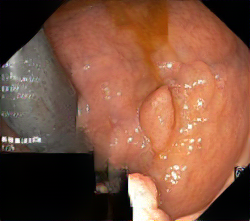

We have used a polyp dataset published with HyperKvasir dataset [51], which consists of polyp findings extracted from endoscopy examinations. HyperKvasir contains polyp images with corresponding segmentation masks annotated by medical experts. We use only this polyp dataset as a case study because of the time and resource-consuming training process of the SinGAN-Seg pipeline. However, the SinGAN-Seg model and pipeline can be used for any segmentation dataset.

A few sample images and the corresponding masks of the polyp dataset in HyperKvasir are shown in Fig 2. The polyp images are RGB images. The masks of the polyp images are single-channel images with white () for true pixels, which represent polyp regions, and black () for false pixels, which represent clean colon or background regions. In this dataset, there are different sizes of polyps. The distribution of polyp sizes as a percentage of the full image size is presented in the histogram plot in Fig 3, and we can observe that there are more relatively small polyps compared to larger polyps. Additionally, a subset of this dataset was used to prove that the performance of segmentation models trained with small datasets can be improved using our SinGAN-Seg pipeline, and the whole dataset was used to show the effect of using SinGAN-Seg generated synthetic images instead of a large dataset which has enough data to train segmentation models. In this regard, this dataset was used for two purposes: